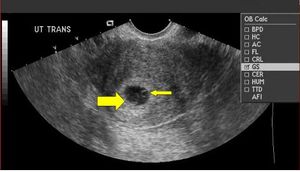

Definite IUP = gestational sac containing yolk sac

- Occurs ~5.5th week

- MUST contain yolk sac to be confirmed IUP. Pseudogestational sac possible in ectopic pregnancy